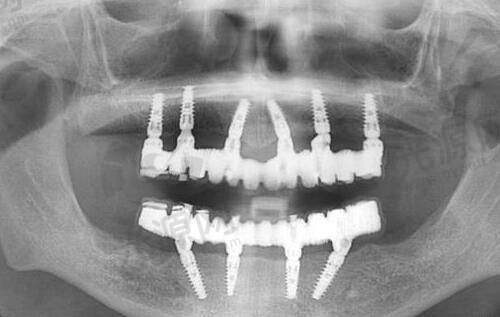

深圳格伦菲尔口腔医院种植牙技术实力剖析

深圳格伦菲尔口腔医院在种植牙技术方面表现出色。医院的医生团队实力雄厚,例如姜伟涛医生,从事口腔工作有几十年的经验,种植及正畸都能做,可以做疑难种植、数字化即刻种植、牙齿正畸、疑难正畸修复、美白修复以及口腔各种修复植体的应用等项目。阳金楚医生在种植方面经验也比较丰富,可以做疑难种植、微创种植、微创即刻种植、颌面外科治疗、前牙美学修复设计等。

医院还采用了多种精良的种植牙技术。即刻负重技术让牙槽骨条件好的患者,上午种牙,下午戴临时冠,吃饭社交两不误;数字化导板种植术前进行3D建模,避开神经血管,误差控制在0.2mm内,对怕疼的患者十分友好;骨增量方案针对牙槽骨萎缩,采用胶原骨粉+自体PRF生长因子,愈合速度提升30%。